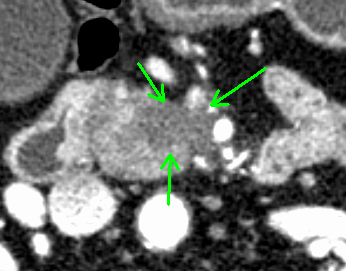

術前化学療法の治療例

治療前

治療後